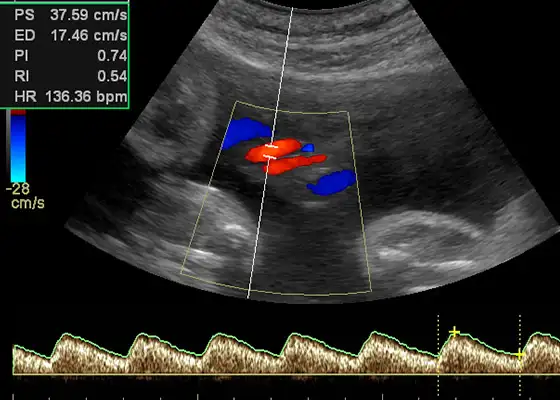

Darstellung von Blutfluss und Gefäßstrukturen – wichtig für die Abklärung von Zysten, Myomen und anderen Veränderungen.